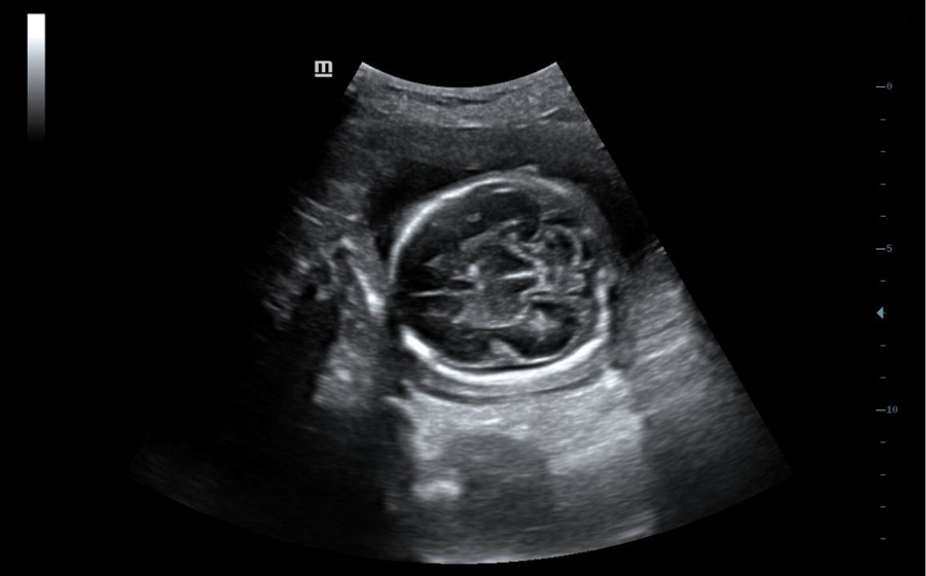

Ilustraciones anatĂłmicas normales que incluyen imĂĄgenes esquemĂĄticas y ecogrĂĄficas.

VisualizaciĂłn lateral de ultrasonografĂas estĂĄndares que proporciona orientaciĂłn visual sobre la regiĂłn de interĂ©s.

ImĂĄgenes de ecografĂas estĂĄndares

3

ComparaciĂłn de ecografĂas en tiempo real para su referencia.

ImĂĄgenes de ecografĂas de referencia

ImĂĄgenes clĂnicas